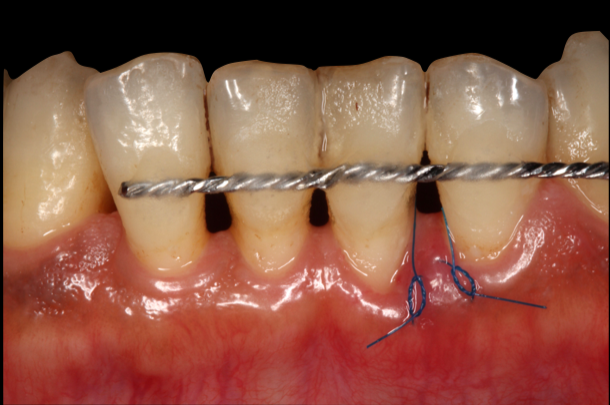

必要に応じて歯の固定

重度歯周病は歯を支える骨が溶かされており、グラグラしている状態です。その歯を固定することでしっかりと噛める状態を作ります。これによりブラッシングがしやすくなるというメリットもあります。